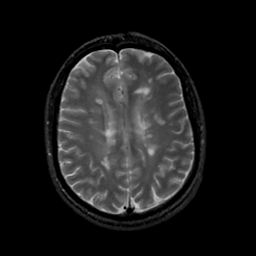

MR Study #18, July 21, 1991 -- Slice #33

[Home][Help][Clinical][Tour 1][Tour 2] Slice 33